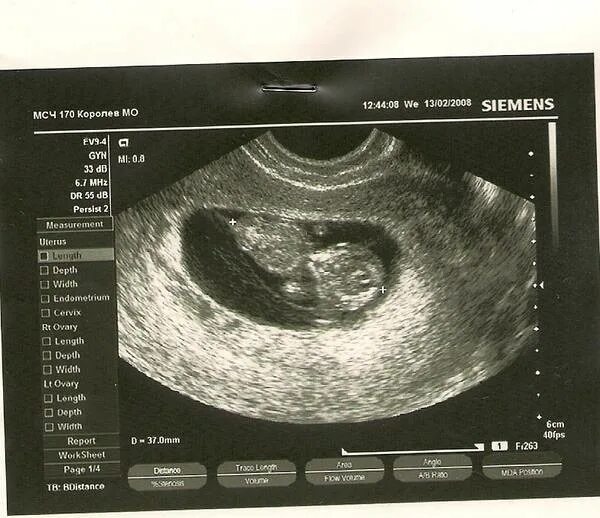

На каком сроке увидели плодное яйцо